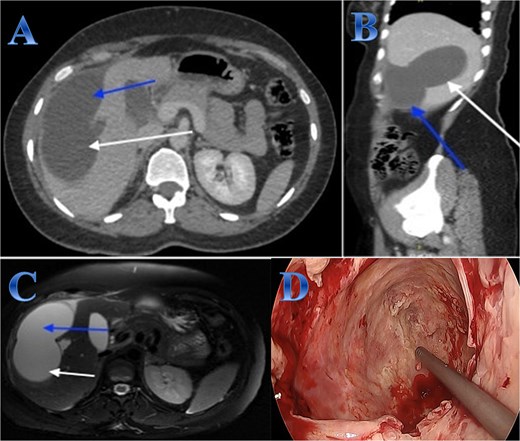

A 31-year-old male presented with a 5-days history of epigastric pain accompanied by jaundice, darkened urine, together with a clay stool. On examination, there was jaundice with epigastric tenderness. Clinical tests showed increased total and direct bilirubin levels. CT showed left hepatic lobe exophytic CE (Fig. 4).

Case 4. (A & B) Post-contrast CT cuts showing well-defined cystic lesion showing internal daughter cysts noted at the left hepatic lobe and seen exophytic indenting the lesser curvature of the stomach, septate lesion is seen in the left lobe of the liver (photo A). The lesion is abutting the lesser curvature of the stomach with intact fat planes between the two (photo A). (C & D) MRI cuts showing well-defined, septate lesion, abutting the lesser curvature of the stomach. The lesion makes some mass effect off the left hepatic biliary radicles communicating with the lesion (photo C).

The patient underwent ERCP for biliary drainage. Subsequent follow-up revealed improved jaundice and reduced pain; at that time, the patient was started on albendazole, which continued for 2 months. The patient was admitted for surgery, and laparoscopic left lateral resection was done. After liver mobilization was done by detaching the falciform, left triangular and coronary ligaments to mobilize the left liver lobe. Retraction of the left lateral segment was performed to expose segments 2 and 3 which were isolated using laparoscopic gauze soaked in hypertonic saline A harmonic scalpel was used for parenchyma transection, and the left bile duct was identified between segments 4 and 2 and 3, which was transected using endovascular gastrointestinal stabler (endo-GIA). Before ending the parenchyma dissection upward, the left hepatic vein was identified and divided using endo-GIA (Fig. 4).